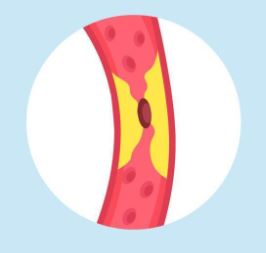

A stroke is when there is not enough blood in the brain. It could be because:

|

The heart may not be able to pump blood to the brain very well so the blood forms sticky clumps that causes a blockage. Doctor’s call these clumps ‘clots’

|

|

Sticky clumps or fat may build up inside the tubes and stop the blood from flowing |

|